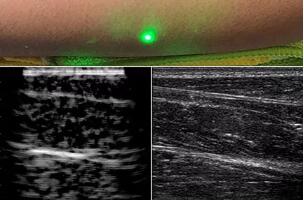

目前,研究人員已經(jīng)與健康的志愿者測(cè)試了他們的系統(tǒng):從半米遠(yuǎn)處掃描了他們的前臂,并將這些結(jié)果與傳統(tǒng)超聲的結(jié)果進(jìn)行了比較。他們能夠觀察到深達(dá)6厘米的組織,并能看到肌肉,脂肪和骨頭,并報(bào)告其結(jié)果可與標(biāo)準(zhǔn)超聲相媲美。

研究人員用一種激光裝置測(cè)試了這個(gè)想法,該裝置使用一個(gè)波長為1,550納米的脈沖激光來產(chǎn)生聲波,并使用第二個(gè)連續(xù)激光,調(diào)諧到相同的波長以遠(yuǎn)程檢測(cè)反射的聲波。第二個(gè)激光器是靈敏的運(yùn)動(dòng)檢測(cè)器,可測(cè)量聲波從肌肉,脂肪和其他組織反射回來而引起的皮膚表面振動(dòng)。反射的聲波產(chǎn)生的皮膚表面運(yùn)動(dòng)會(huì)導(dǎo)致激光頻率發(fā)生變化,這種變化可以測(cè)量。通過機(jī)械掃描人體上的激光,科學(xué)家可以獲取不同位置的數(shù)據(jù)并生成該區(qū)域的圖像。